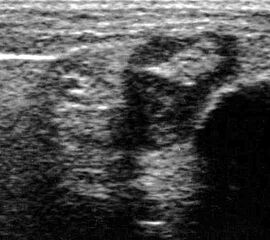

Tendopathien der Flexorensehnen

Dorsaler TS hinter dem Innenknöchel.

Abbildung 46

Lagerung: Rückenlage, Außendrehung des Beines.

Schnittführung: TS und LS hinter dem Innenknöchel beginnen und bis zum Os cuneiforme mediale fortführen.

Referenzstrukturen: Innenknöchel, Talus, Os naviculare, Os cuneiforme mediale, Sehnen der Mm tibialis posterior, flexor hallucis longus, flexor digitorum.

Befunde: Häufig betreffen die Pathologen die Tibialis-posterior-Sehne, die als erste Sehne hinter dem Innenknöchel zur Darstellung kommt. Halo-Phänomen und echoarme Verdickung bei akuter Tendinopathie, zunehmend inhomogen und echogen mit Kaliberschwankungen bis hin zu Teilrupturen bei Chronifizierung 5. Für die Erkennung von Teilrupturen sind TS in verschiedener Höhe besonders wichtig. Bei komplettem Riss mit Retraktion im LS Bild wie Spargelspitze mit umgebender Flüssigkeit oder Hämatom. Ein Os tibiale externum erscheint als echoreiche Struktur im Verlauf der Tibialis posterior Sehne mit dorsaler Schallauslöschung. Ein Os naviculare cornutum imponiert als starke Prominenz im Ansatzbereich der Tibialis posterior Sehne.